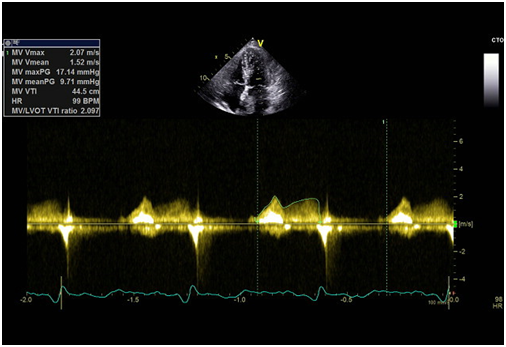

We report a case of a 57-year-old female, with previous history of smoking, hyperlipidaemia and history of ischemic stroke without residual deficits. She was ordered a transthoracic echocardiogram (ETT) to rule out cardiac embolism which revealed an echogenic left atrial mass of huge dimensions (5.8x2.8cm) connected by a small pedicle to the interatrial septum and prolapsing into the left ventricle in diastole causing transmitral flow obstruction (Figure 1) (Figure 2). Doppler revealed a mean pressure gradient between left atrium and ventricle of 9.71mmHg (Figure 3). Transthoracic 3D echocardiography allowed a better characterization of the mass and its attachment to the interatrial septum (Figure 4).

Figure 3 Transmitral doppler flow showing the elevated mean pressure gradient between left atrium and ventricle.

Figure 4 3D echocardiographic image showing giant left atrial myxoma.